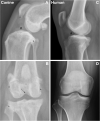

Canine ACL rupture: a spontaneous large animal model of human ACL rupture

Background: Anterior cruciate ligament (ACL) rupture in humans is a common condition associated with knee pain, joint instability, and secondary osteoarthritis (OA). Surgical treatment with an intraarticular graft provides reasonable outcomes at mid and long-term follow-up. Non-modifiable and modifiable factors influence risk of ACL rupture. The etiology, mechanobiology, causal biomechanics, and causal molecular pathways are not fully understood. The dog model has shared features of ACL rupture that make it a valuable spontaneous preclinical animal model. In this article, we review shared and contrasting features of ACL rupture in the two species and present information supporting spontaneous canine ACL rupture as a potentially useful preclinical model of human ACL rupture with a very large subject population.

Results: ACL rupture is more common in dogs than in humans and is diagnosed and treated using similar approaches to that of human patients. Development of OA occurs in both species, but progression is more rapid in the dog, and is often present at diagnosis. Use of client-owned dogs for ACL research could reveal impactful molecular pathways, underlying causal genetic variants, biomechanical effects of specific treatments, and opportunities to discover new treatment and prevention targets. Knowledge of the genetic contribution to ACL rupture is more advanced in dogs than in humans. In dogs, ACL rupture has a polygenetic architecture with moderate heritability. Heritability of human ACL rupture has not been estimated.